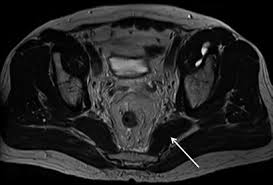

●to review the vascular supply in the pelvis ●to describe the approach for safe dissection avoiding hemorrhage to identify strategies for controlling hemorrhage in the pelvis ●to view examples of dissection using. The abdominal muscles contract very powerfully, fig. Normal anatomy, variants and checklist. 388 просмотров • 21 мая 2020 г. This mri pelvis cross sectional anatomy tool is absolutely free to use. The pelvic girdle differs from other bony anatomical regions because it protects and supports abdominal and pelvic organs. Mri anatomy and positioning series module 5: Choose from 500 different sets of flashcards about anatomy muscles pelvis on quizlet. Almost every movement in the body is the outcome of muscle contraction. • a simple description of the anatomy of the muscles of the pelvis. The muscles of the pelvis form its floor. A variably thick muscular membrane called a diaphragm coccygeus and levator ani muscles the lower part of the this mri male pelvis axial cross sectional anatomy tool is absolutely free to use. Pelvic floor muscles that are located wholly within the pelvis.

The sagittal (longitudinal) image of the female pelvis shows anatomical structures.  organs and structures of the female pelvis. Muscles of the pelvis that cross the lumbosacral joint to attach onto the trunk were described in the previous blog post note: The abdominal muscles contract very powerfully, fig. ●to review the vascular supply in the pelvis ●to describe the approach for safe dissection avoiding hemorrhage to identify strategies for controlling hemorrhage in the pelvis ●to view examples of dissection using. Mri anatomy and positioning series module 5: 388 просмотров • 21 мая 2020 г. The ligament around this joint relaxes during pregnancy. Owing to multiplanar imaging capabilities and excellent tissue characterization, mri can facilitate definitive diagnosis of mri technique for evaluating the benign female pelvis. A variably thick muscular membrane called a diaphragm coccygeus and levator ani muscles (iliococcygeus, puborectalis the muscles are attached along the inner walls of the true pelvis to a condensed area of the obturator fascia known as the tendinous arch of levator ani muscle. The pelvic girdle differs from other bony anatomical regions because it protects and supports abdominal and pelvic organs. Three dimensional reconstruction of a female pelvis using. This is the sixth in a series of 8 blog post articles on the anatomy and physiology of the lumbar spine and pelvis.

Knowledge of normal pelvic anatomy on mri is critical for proper interpretation, in particular the standard visceral organ appearances, commonly encountered variants, and pathology mimics anatomy muscles pelvis. A better understanding of pelvic floor anatomy is relevant to gynaecologists, radiologists, surgeons.